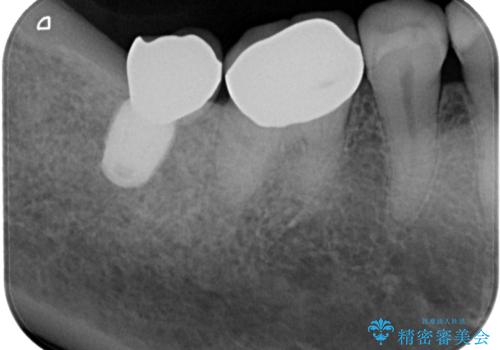

理想的な咬み合わせに改善した上で、インプラント補綴治療を行うこととしました。

部分矯正を行ったこと治療期間は長くなりましたが、違和感のない咬み合わせを達成することができました。